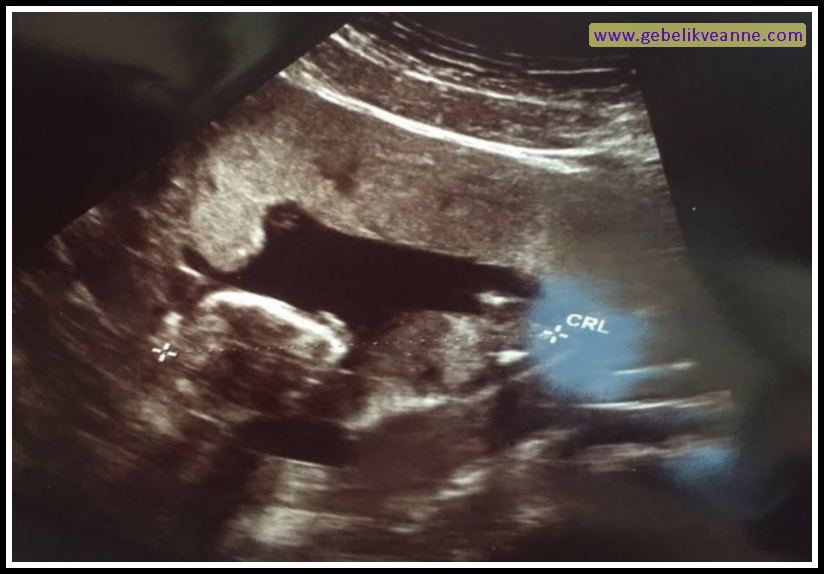

17 Haftalık Bebek Ultrason Görüntüsü Dailymotion Video

17 Haftalık Gebelik (Hamilelik) Ultrason Görüntüleri

Ayında anne karnında bebeğin durumu nasıldır. 40 hafta boyunca her hafta biraz daha yaklaşırsınız ona. Haftada bebeğinizle hemen hemen aynı büyüklüğe ulaşır. 17 haftalık gebelik görüntüsü incelendiğinde bebeğin boyunun önceki haftanın neredeyse iki katı olduğu görülür. Bu nedenle sık sık yeme ihtiyacı hissedebilirsiniz. 17.haftayla beraber bebeğin cilt altında yağlanma başlayacaktır bebeğinizin görünümü artık insan görünümüne kavuşmuştur. 17 haftalık hamilelikte 4 boyutlu ultrason görüntüsü. 17 haftalık bebek hissedilir mi?

Bir genetik hastalığı olduğunu bilen ve genetik incelemesi yapılan çiftlerde normal tüp bebek prosedürü uygulanır. 17 haftalık hamilelikte 3d , 4d boyutlu ultrason görüntüsü.17 hafta gebelik ultrason görüntüleri17 haftalık gebelikte anne karnında bebeğin görüntüsü, 17 haf. Bebeğin kalp atışlarının hızı düşmeye devam ediyor.